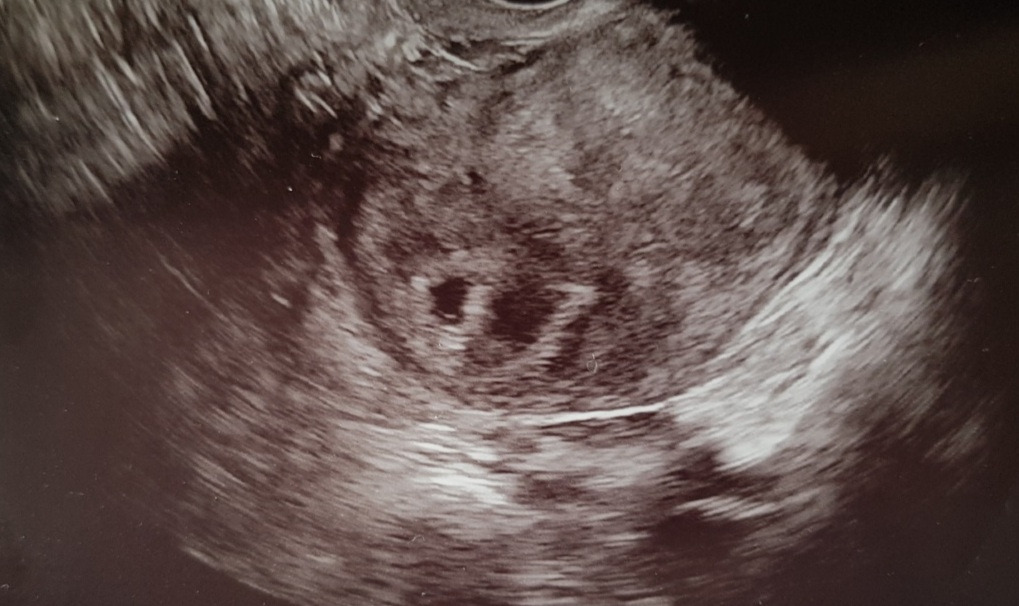

아기 콩이의 임신을 처음 확인한 날. 가운데 왼쪽의 작은 검은 부분이 콩이의 '아기집'이다.

초음파 검사로 임신 사실을 눈으로 처음 확인했던 날 우리가 볼 수 있었던 것은 바로 ‘아기집’이었다. 아기집은 말 그대로 아기가 자라는 집으로 아기가 자랄수록 아기집은 커지며, 그 안은 양수로 채워진다. 물론 우리가 아기집을 처음 본 임신 5주 차에는 그 크기가 집이라고 부르기에는 민망할 정도로 앙증맞았고, 그 안의 집주인의 모습은 확인하기가 어려웠다. 아직까지는 아기가 너무 작아서 초음파 검사로 식별이 불가능했기 때문이다.